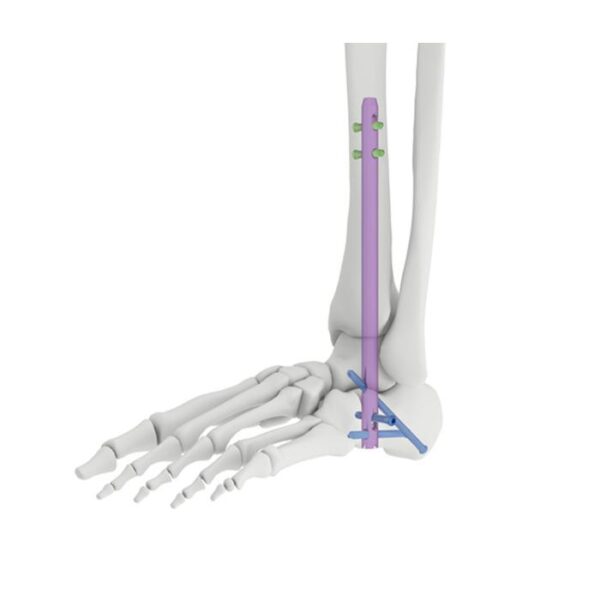

Clavo de artrodesis de tobillo:

Orificios de bloqueo estáticos y dinámicos:

- Proporcione orificios de bloqueo estáticos y dinámicos en el proximal.

Tornillos distales para cepillado múltiple que cruzan los orificios de bloqueo:

- Fijación de articulaciones cruzadas para mejorar la estabilidad de la fusión.

- El tornillo se inserta oblicuamente en la apófisis anterior del calcáneo o en la articulación calcáneo-cuboidea para mejorar la fuerza y la estabilidad de extracción.

Tornillos de bloqueo:

- Agujeros proximales dinámicos y estáticos con tornillo de bloqueo de 5.0 mm.

- Tres orificios transversales distales coinciden con el tornillo de bloqueo de 6,0 mm.